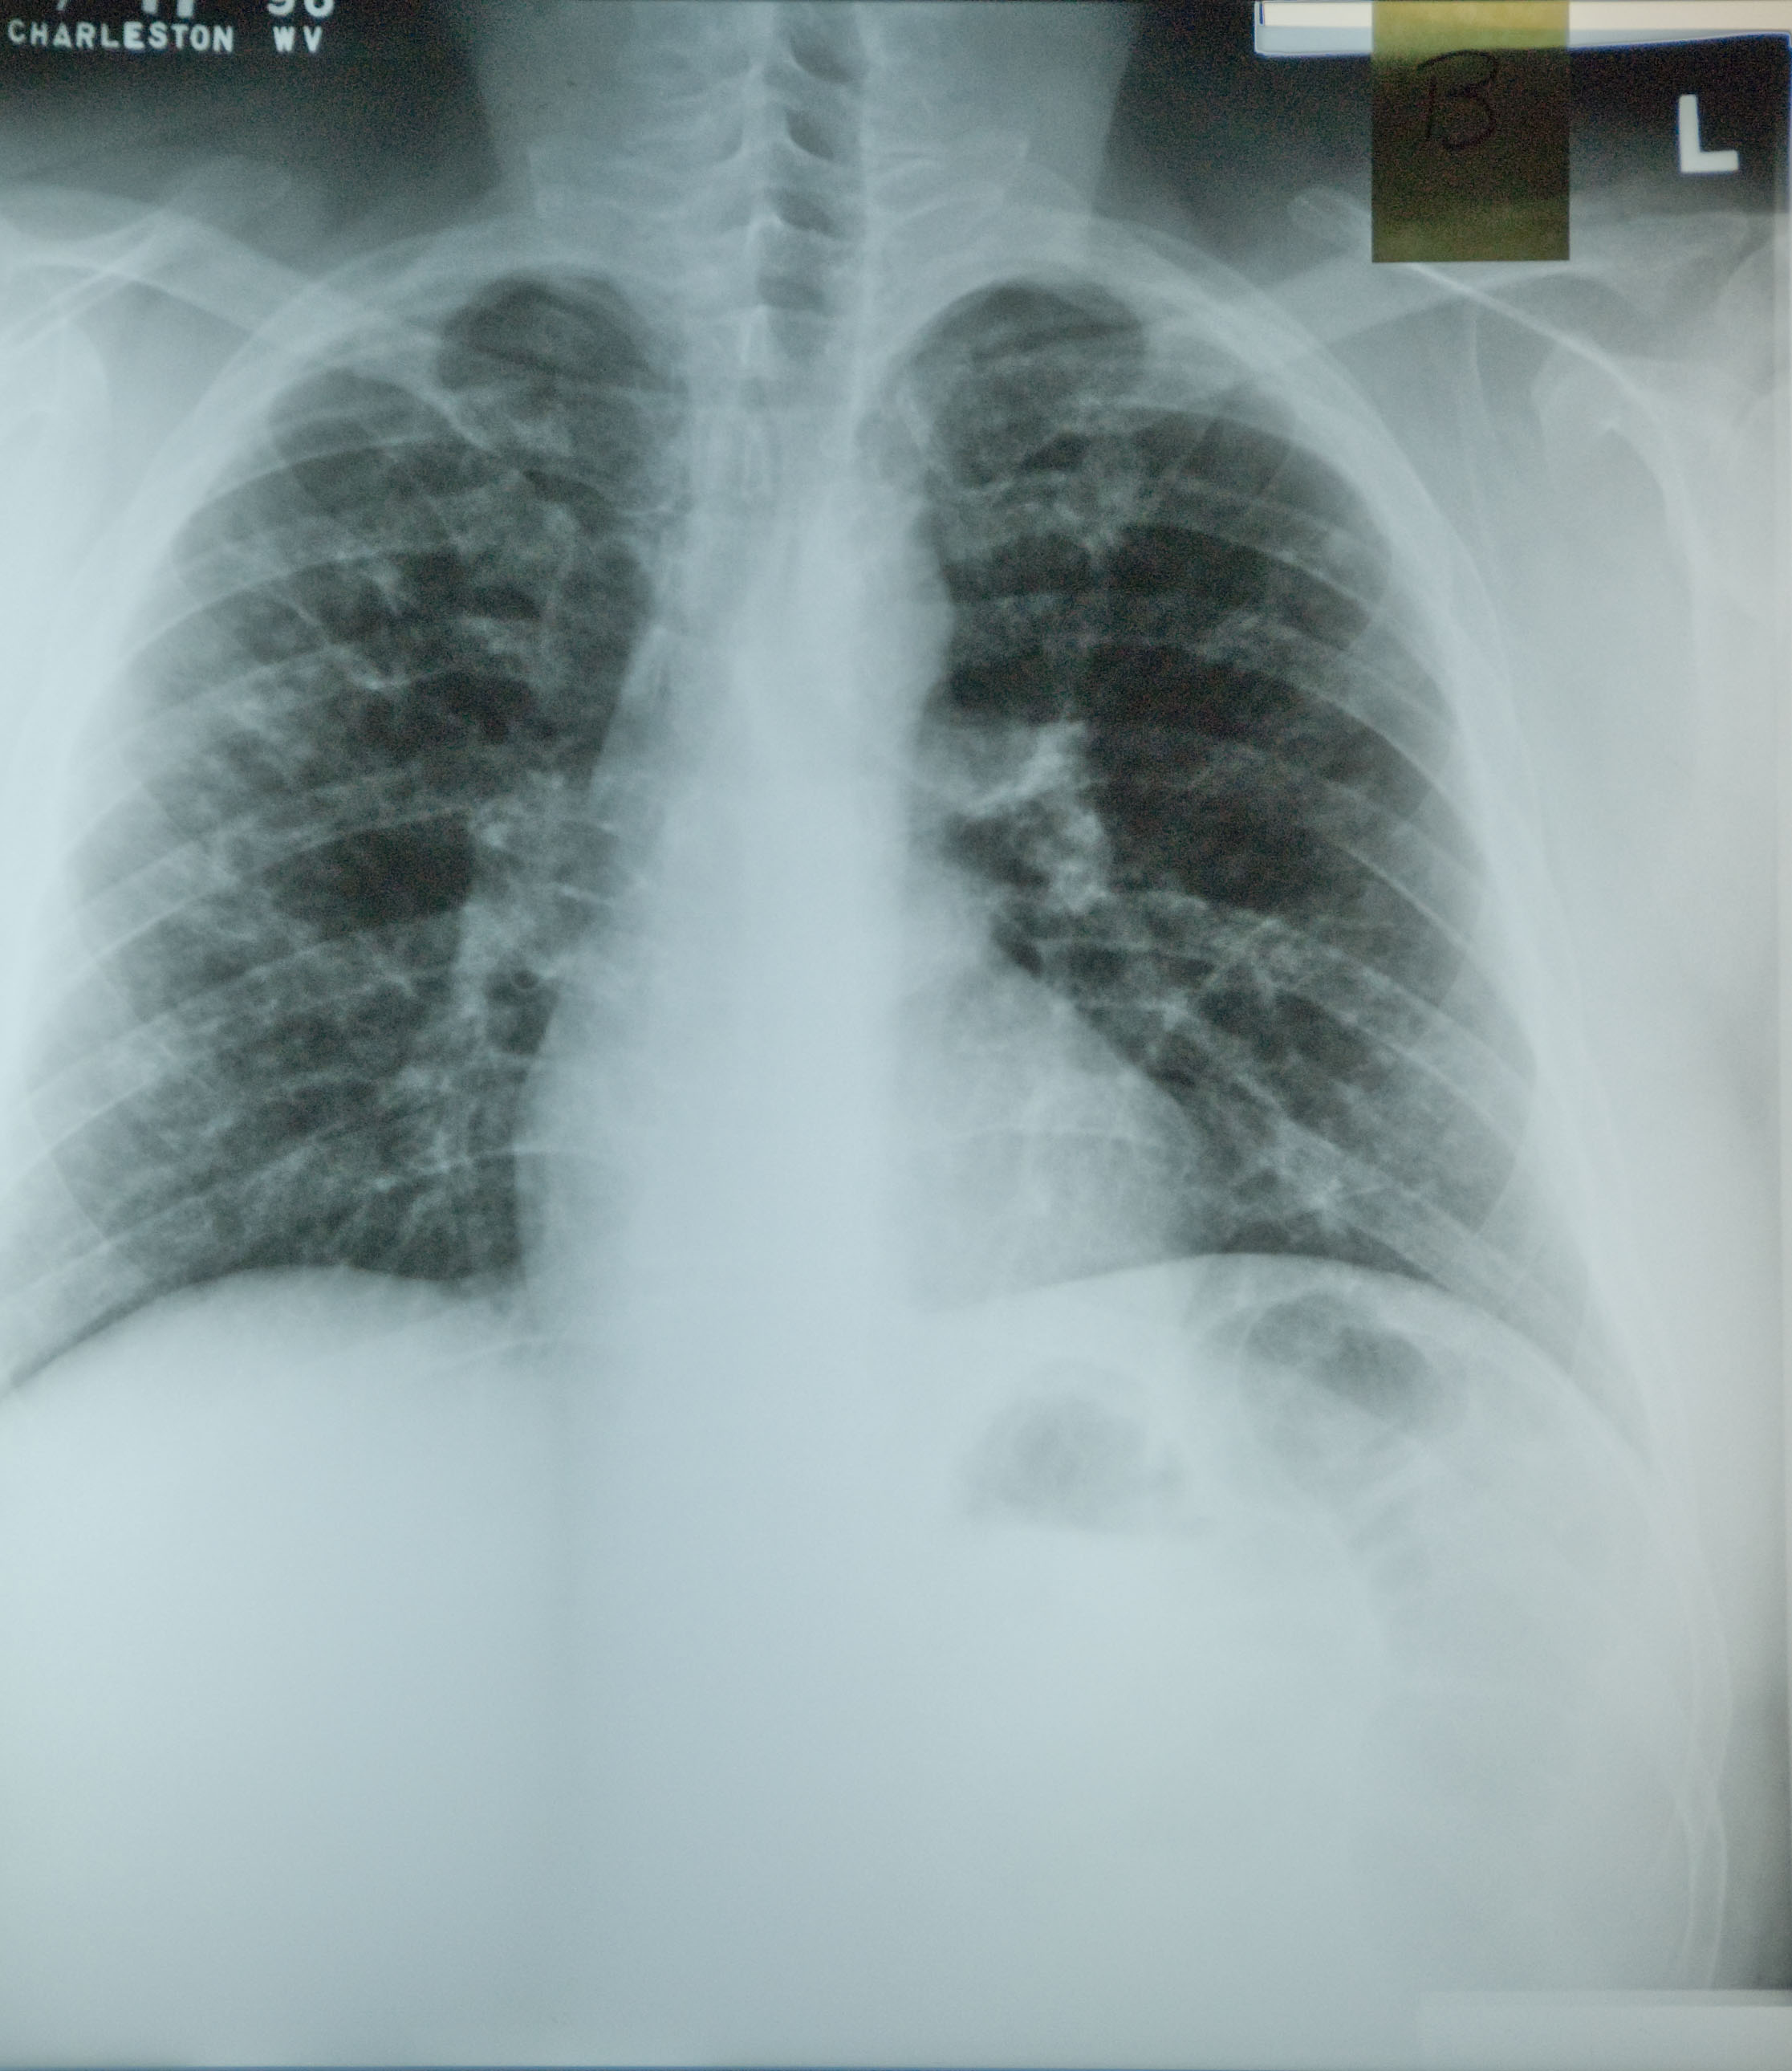

A chest radiograph was taken at that time (Figure 1.3).

Figure 1.3

Both coal and silica dust exposures trigger inflammation of the airways and the interstitium, and pneumoconiosis can continue to progress for years after termination of all dust exposure (1). This is one reason why primary prevention through dust control is critical. Inflammatory nodules can coalesce to form PMF (also called complicated pneumoconiosis), which is recognized on the chest radiograph as one or more lesions 10mm in diameter or greater. After PMF develops, the fibrosis and associated emphysema often progress even without further dust exposure, as was the case with this patient. Adjacent lung parenchyma is pulled towards the lesions, which most typically occur in the upper lung. The large airways are distorted as lung volume is lost and lung function may show obstructive and/or restrictive impairments.